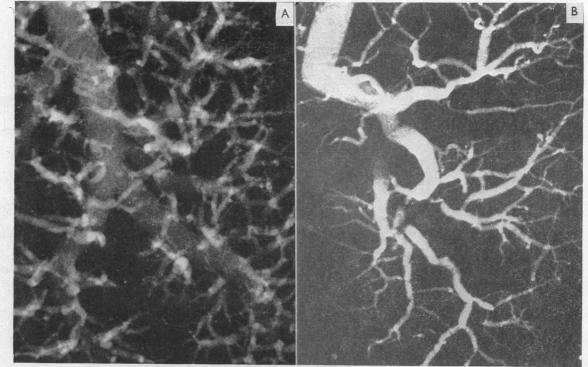

Solitary pulmonary hypertension.

Br Heart J. 1957 Jan;19(1):93-116. doi: 10.1136/hrt.19.1.93.